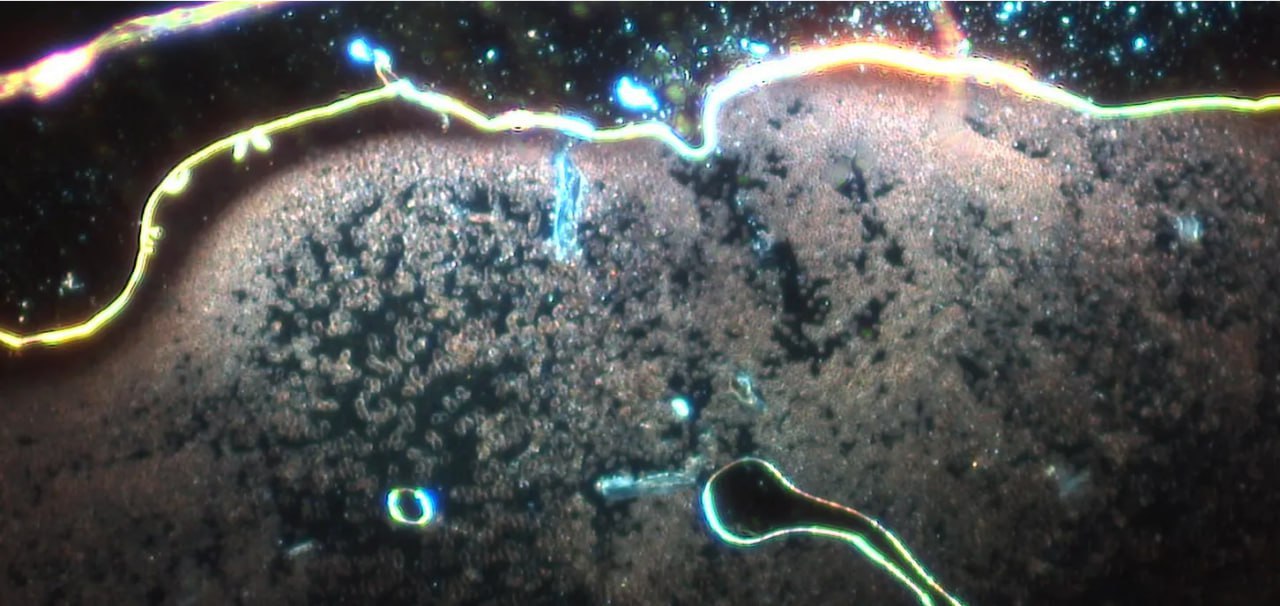

Zum Schluss noch ein abschreckendes Beispiel von Dunkelfeld-Aufnahmen.

Folgendes Bild wurde u.a. auf telegram geteilt:

Wir sehen hier in deutlich geringerer Vergrößerung auch Blut. Allerdings sehen wir hier vor allem den Rand des Bluttropfens (oben). Die Ränder sehen mehr oder weniger fast immer so aus. Was wir hier allerdings sehen ist ein stark verschmutzter Objektträger (helle Objekte ganz oben). Zudem sehen wir Lufteinschlüsse im Präparat.

Das könnte man alles als „Anfänger-Fehler“ bezeichnen. In der Praxis würde ich einem Assistenten anweisen, diese Probe zu verwerfen und eine neue Entnahme durchzuführen.

Aber wir haben noch das Problem, dass solche Bilder gezeigt werden und behauptet wird, dass hier die Folgen einer Corona-Impfung deutlich zu sehen seien, inklusive Nanotechnologie, usw. Ich halte das für blanken Unsinn, dies aus diesem Bild hier abzuleiten.

Indes: es gibt „vernünftige“ Aufnahmen, welche die Problematik bei Patienten zeigen, die nach Corona-Impfungen mit Problemen zu tun hatten.